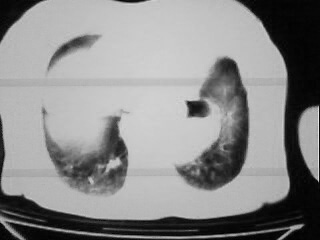

女,79,咳 嗽月余,无其它不适

1)两肺炎症。2)食管裂孔疝可能;建议行上消化道钡餐检查。

后纵隔内左心房至肝左叶后方椎体中线偏左巨大软组织包块,其壁均匀比较薄,其内可见宽气液平。

考虑食管裂孔疝。建议钡餐检查